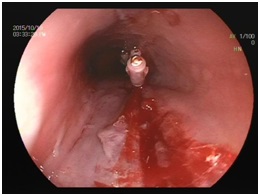

还有一些服药时卡在食管里的情况。一种情况是服药时喝水不够,一些胶囊类的药品会粘在食管壁上,时间长了会形成一个溃疡,并且会有吞咽痛,甚至会出血。另一种情况在老年人比较常见,由于需要服用很多种药物,一些老年人会提前将一周的药品分装好,然后按日期和早中晚去服用,这本来是一个很好的习惯,但是分装药品时,处于卫生的考虑,很多人并不是把药片从铝箔包装里挖出来,而是把一板药的包装一片片剪开,但是吃的时候又没有看清,就连药片带铝箔包装一起吞下去了。由于铝箔包装非常锋利,划破食管的情况屡屡发生。老年患者往往基础疾病较多,胃镜的风险大,甚至无法耐受,处理起来非常棘手。其实可以在分装药片前仔细洗手,或者练习使用专门的钝头镊子,再或者让家里的年轻人代劳,把每一粒药都取出来分装,服药时也略加小心,就可以避免此类事故的发生。

图(4)食管内,铝箔包装的药片,后图是取出来的异物